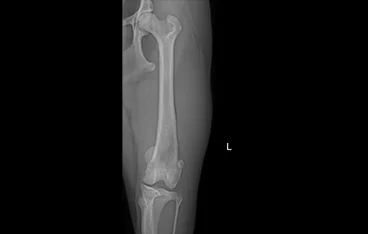

• PLATE 수술 전

PLATE 수술 후